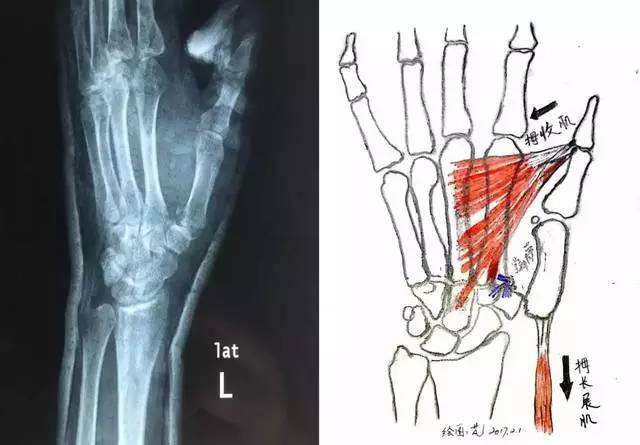

知识点5:拇内收肌是由尺神经支配。为什么单独拿出来讲,因为这是我们需要了解的唯一一块肌肉,和感觉区域不一致。尺神经损伤,这块肌肉就没有功能,拇指不能内收。

知识点7:尺神经支配小鱼际肌、全部骨间肌和3、4蚓状肌、拇内收肌等。

骨间肌和蚓状肌的作用一样,都是屈掌指关节伸指关节。尺神经损伤后,不能起到这个功能,就只能伸掌指关节,屈指关节了,加上拇指外展,小鱼际肌萎缩,于是就是下图的爪形手。